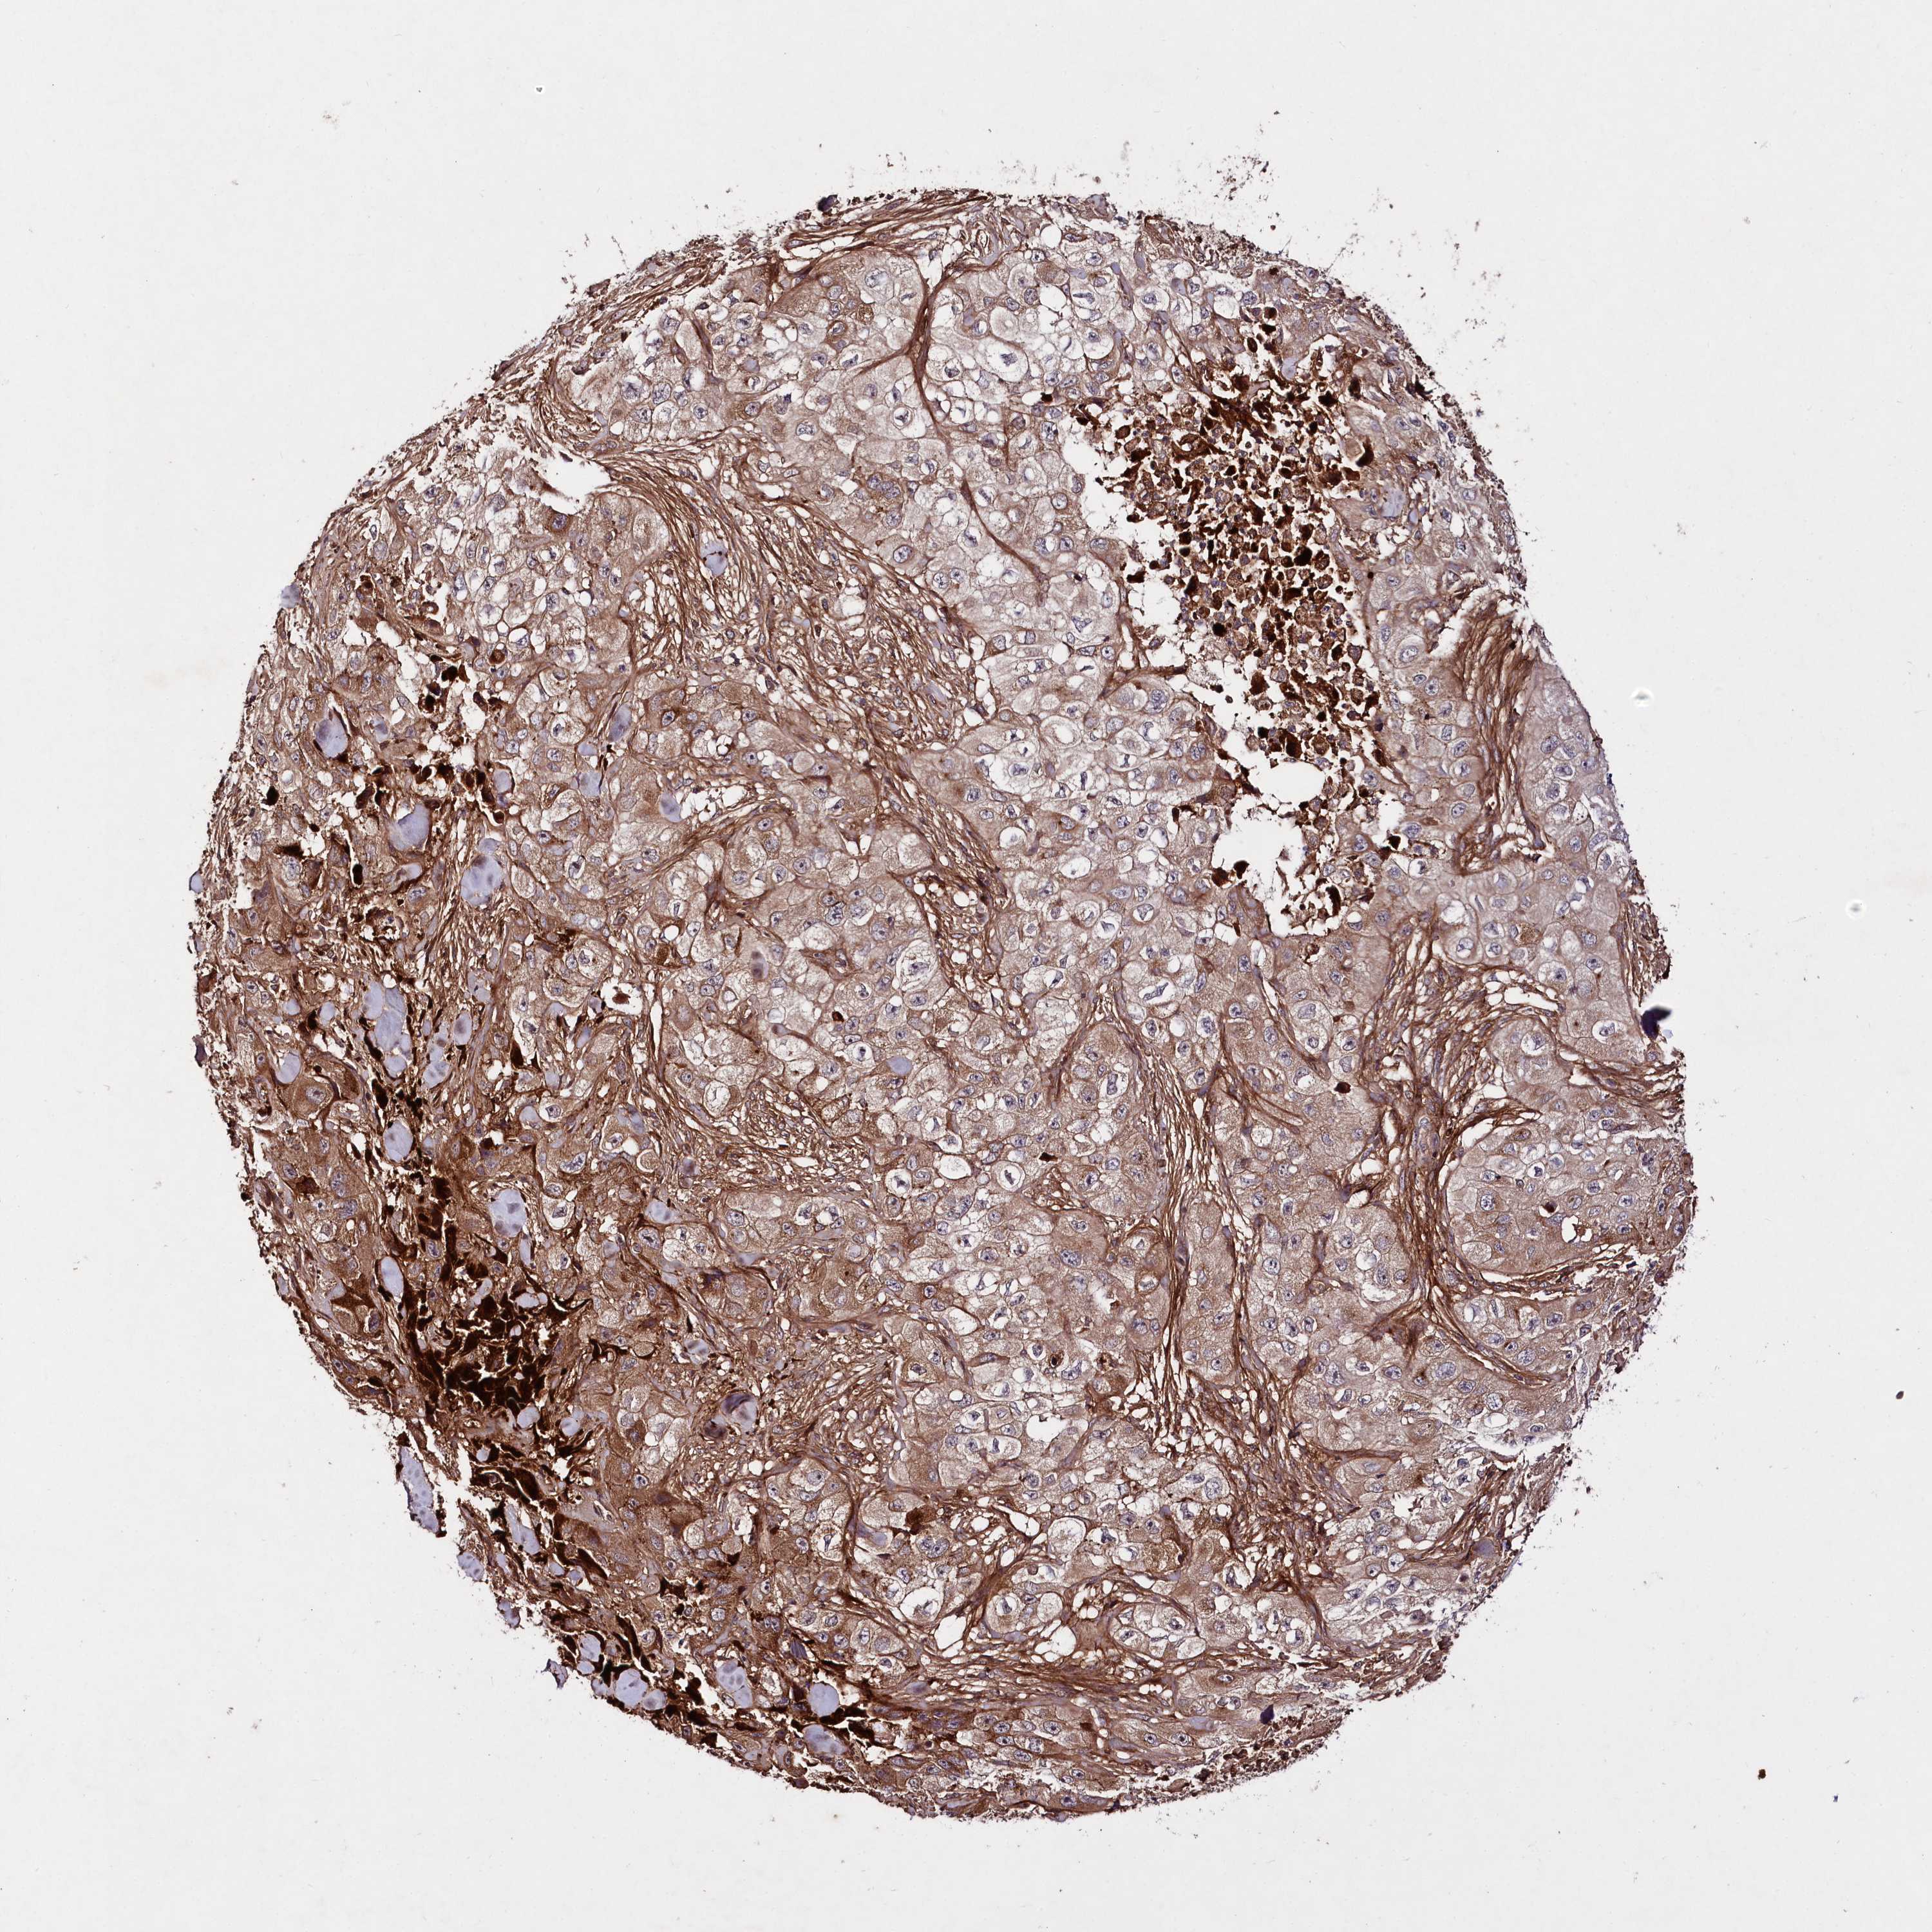

SKIN CANCER - Protein expressioni

A mouse-over function shows sample information and annotation data. Click on an image to view it in a full screen mode. Samples can be filtered based on level of antibody staining by selecting one or several of the following categories: high, medium, low and not detected. The assay and annotation is described here.

Antibody staining in the annotated cell types in the current human tissue is reported as not detected, low, medium, or high, based on conventional immunohistochemistry profiling in selected tissues. This score is based on the combination of the staining intensity and fraction of stained cells.

Each image is clickable and will lead to virtual microscopy that enables deeper exploration of all samples and also displays staining intensity scores, fraction scores and subcellular localization as well as patient and tissue information for each sample.

Antibody HPA039555

Staining

High

Basal cell carcinoma